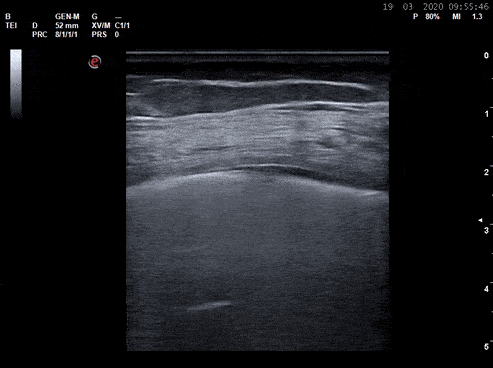

Pulmonary - Common Pleural Based Findings in COVID-19

Lung ultrasound performed in a COVID+ patient. Note the clustered B lines, patchy shredding (depression) and thickening of pleural line, and small sub-pleural consolidations. Image courtesy of Dr. Marco Garrone (@drmarcogarrone)